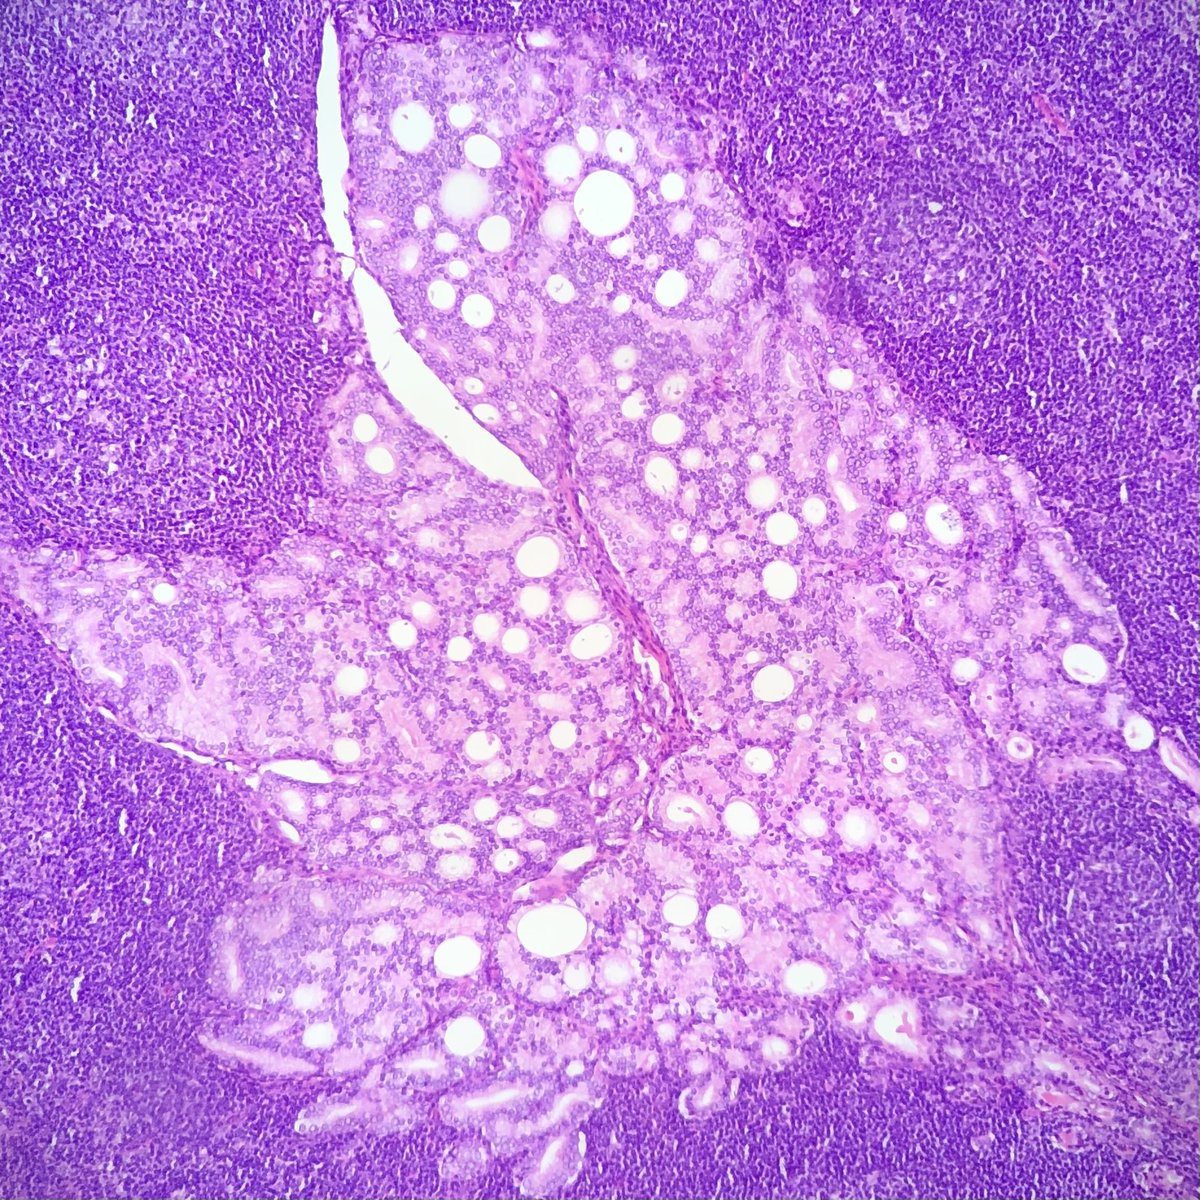

Illustration of a case of Follicular Lymphoma with Hyaline Vascular Unicentric Castleman Disease-"like" changes➡️

🩸Depleted germinal centers (Fig 2)

🩸Onion-skinning of mantle zones (Fig 2-3)

🩸Penetrating hyalinized vessels, imparting a lollipop-like configuration of germinal centers (Fig 3)

🩸Twinning (fusion) of follicles (Fig 4)

This case turned out to be postive for BCL2 translocation by FISH, with an aberrant CD10-positive population by flow cytometry analysis.

More on this variant of Follicular Lymphoma➡️pubmed.ncbi.nlm.nih.gov/28873356/

To complicate things, the "follicular variant" of Hyaline Vascular Unicentric Castleman Disease, with characteristic back-to-back follicular architecture, may greatly mimic follicular lymphoma as well ➡️pubmed.ncbi.nlm.nih.gov/8116226/

➡️pubmed.ncbi.nlm.nih.gov/19039195/

In summary, by morphologic examination, Follicular Lymphoma may present like Hyaline Vascular Unicentric Castleman Disease; Conversly, Hyaline Vascular Unicentric Castleman Disease may show a presentation very similar to Follicular Lymphoma